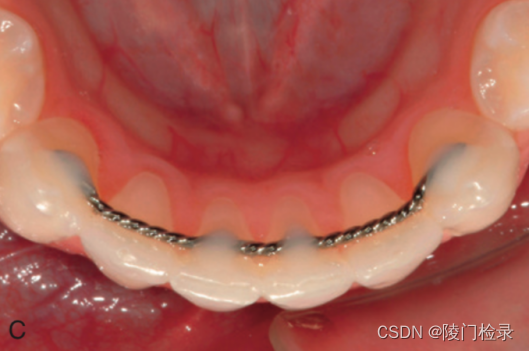

1)舌侧丝保持器是将钢丝用特殊的粘剂粘在牙齿内侧,体积小,从外面基本看到不到,适合不怎么自律的小伙伴。舌侧丝一旦适应之后也不会有什么不适感。

这款保持器只是比较适用前牙扭转拥挤病例,对美观要求极高的病例。以及矫治后,牙槽骨退缩非常明显,也比较适用,但对于大多数患者来说,这类保持器其实并不友好。首先,舌侧丝保持器粘于牙齿内侧,不容易清洁外,很难使用间隙刷,口腔卫生就会变差。价格上比透明保持器要贵。对医生的技术要求比较高。如果医生没粘好,或者胶松了我们很难第一时间发现,这时如果再想进行调整的话,就只能重新粘上矫治器再进行相关位置的调整。